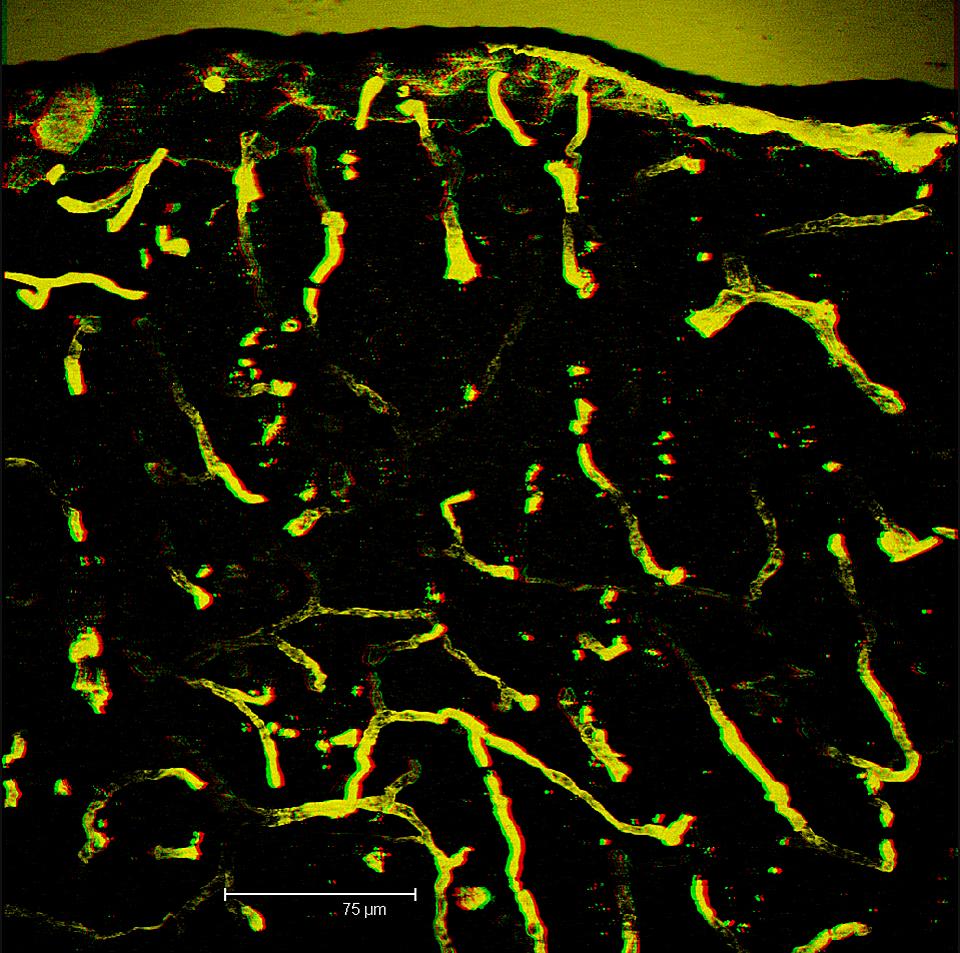

3D transparent projection of a thick section of mouse brain vasculature. Depth of section = 23.90 μm Depth factor 3